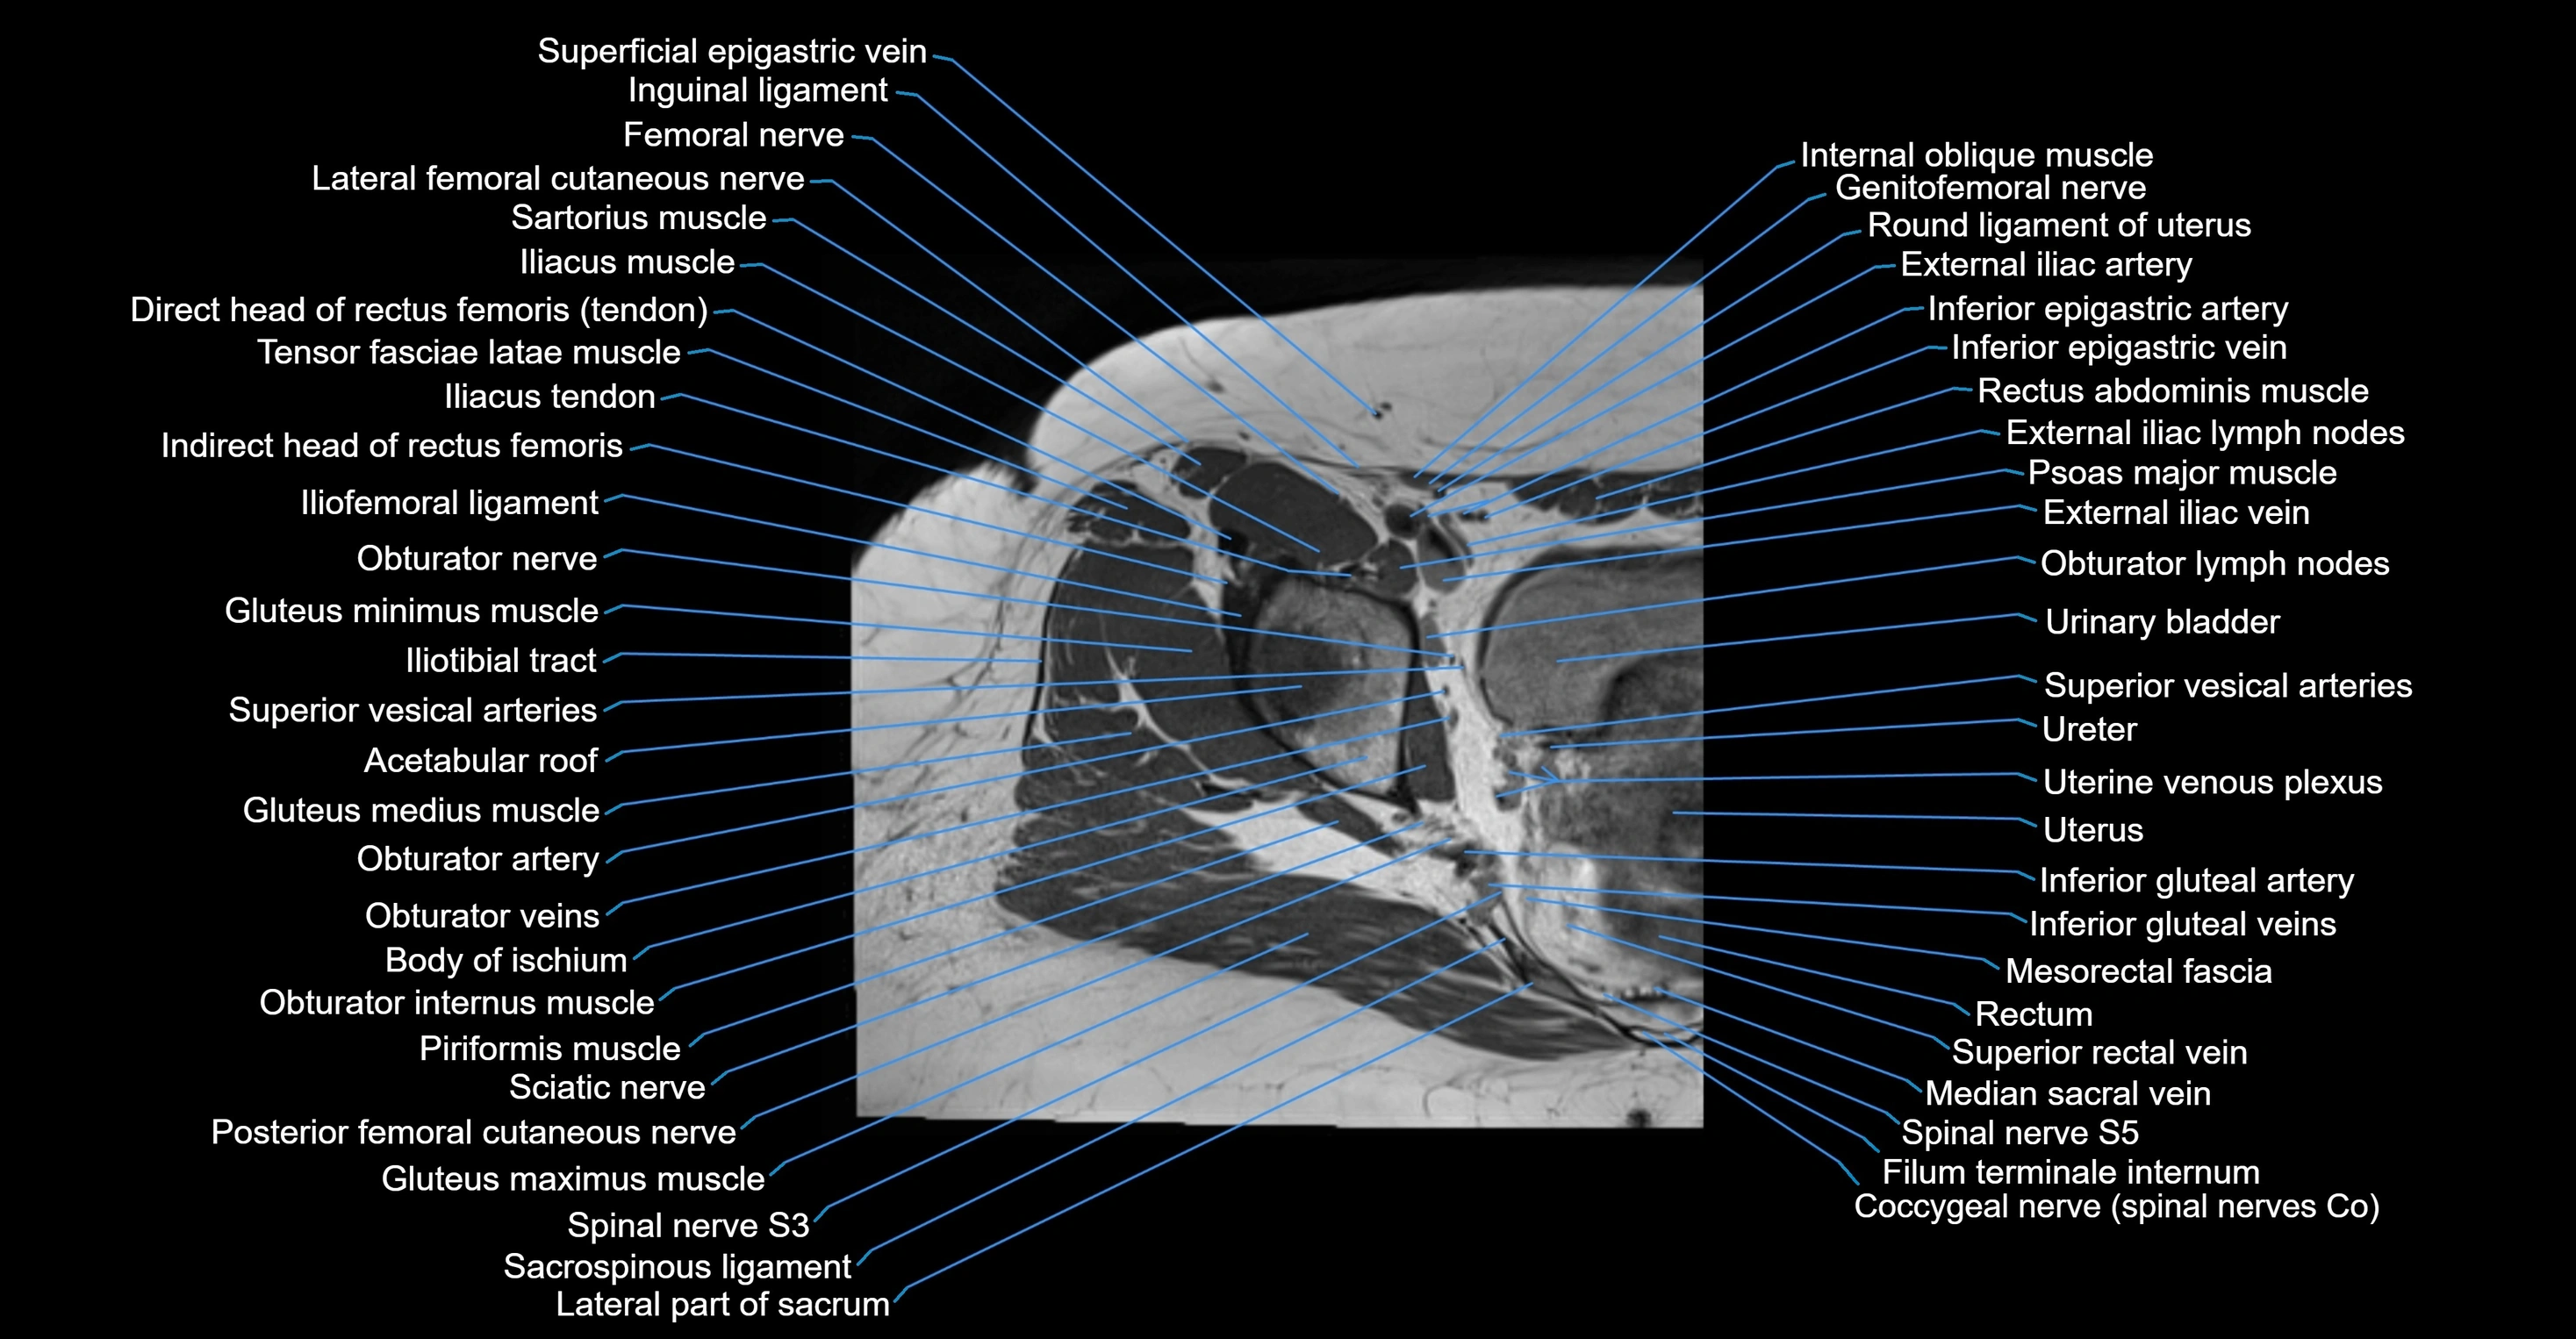

- External iliac artery

- External iliac vein

- Uterus

- Rectum

- Mesorectal fascia

- Median sacral vein

- Filum terminale internum

- Spinal nerve S3

- Spinal nerve S5

- Sacrospinous ligament

- Lateral part of sacrum